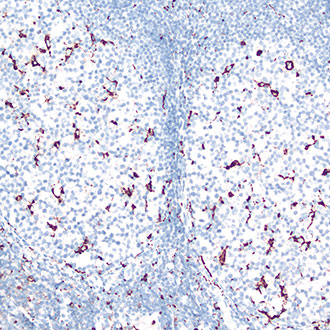

IHC

免疫组织化学(IHC)